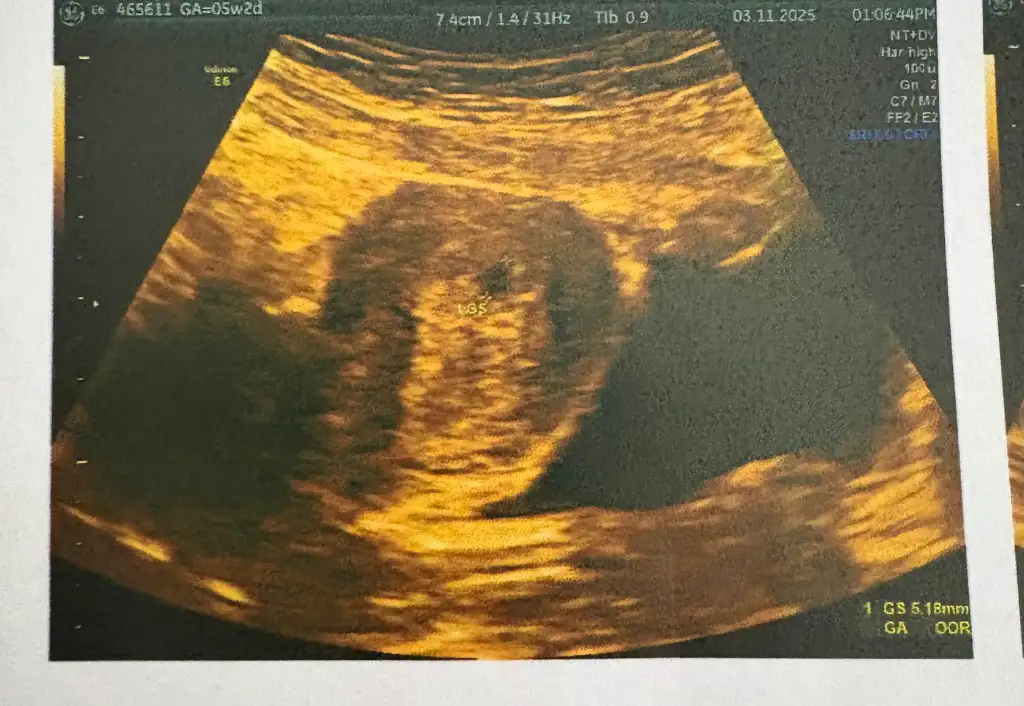

Merhaba hayırlı olsun kaç haftalık görüntü bu bende ayın 17 sine randevü aldım acaba kalp atışını felanda görebilir miyim o zaman 6+3 oluyor